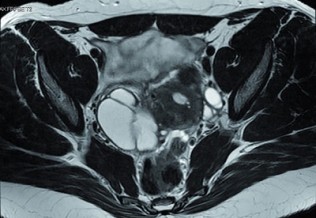

Gynécologie-Obstétrique

Endométriose : vers un remboursement généralisé de l'Endotest ?